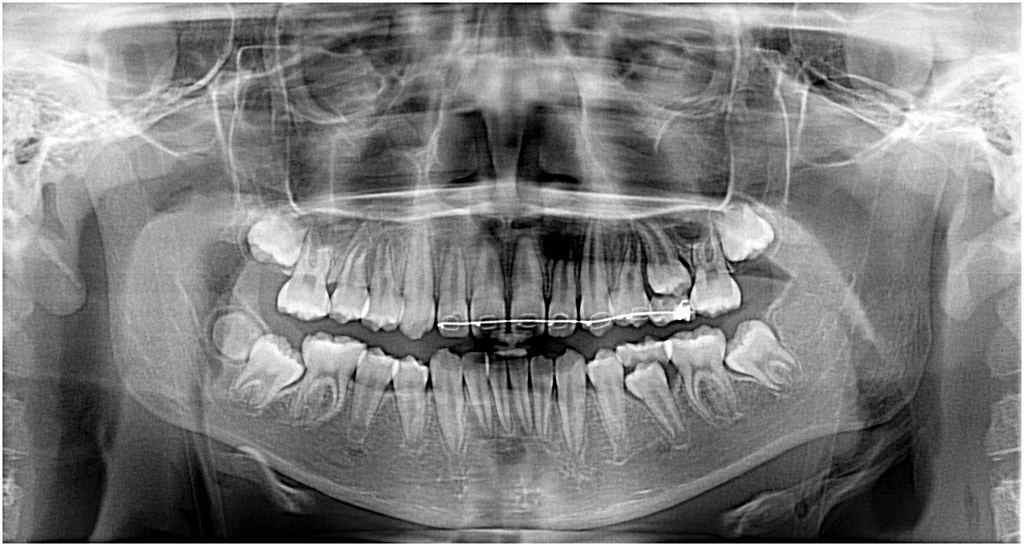

親知らずの早期形成により下顎7番が萌出してこなくなったケース 親知らず抜歯後は早期に萌出してきました

右下7番が萌出してこないのが、親知らずが原因とのことで

抜歯の依頼が来ました

抜歯とともに、一応けん引のことも考え装置を付けていますが

すぐに萌出してきました